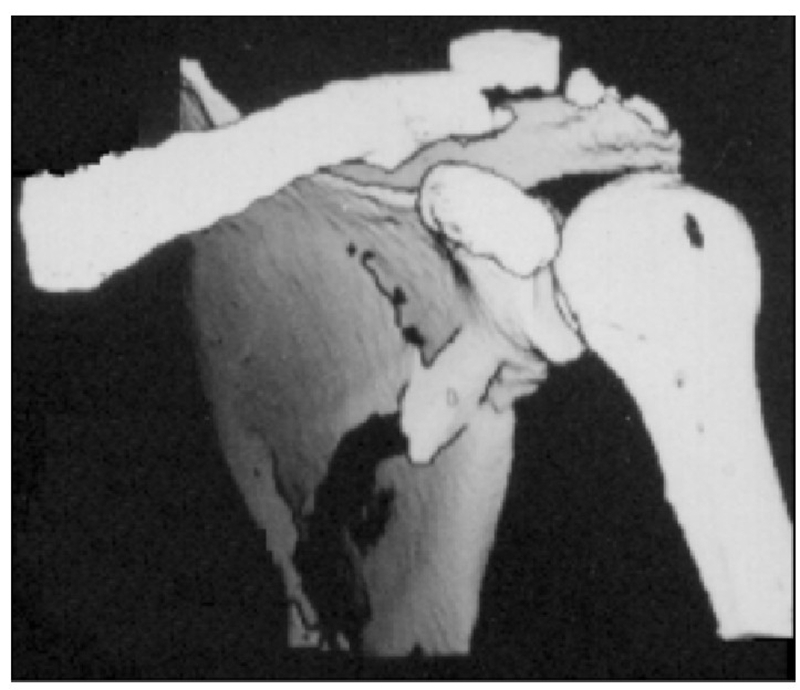

病例2为1例累及肩胛盂、肩胛颈和肩胛骨体部的复杂肩胛骨骨折(图11-12)。

术前设计采用跨骨折区域钢板螺钉固定(图13)。术中可见纵向骨折区域骨质薄弱,骨折粉碎严重,钢板放置位置有限,操作极其困难(图14)。术中采用多块接骨板跨骨折区域固定,术后X线片及三维CT重建显示复位满意(图15)。针对此病例,如果采用缝线辅助固定技术,可使手术操作过程简化,达到同样的固定效果(图16)。

图11 CT三维重建及轴位重建示肩胛骨骨折累及肩胛盂、肩胛颈和肩胛骨体部 图A:CT三维重建;图B:CT轴位重建